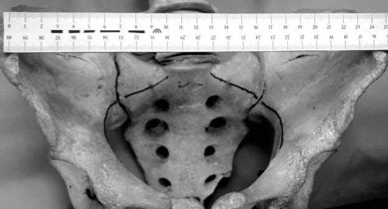

Наиболее часто нестабильные переломы и повреждения тазового кольца имеют место в результате дорожно-транспортных происшествий, несчастных случаев на производстве, падения с высоты 3. При прямом воздействии внешнего агента характер переломов и смещений, их сочетание бывает разнообразным (рис. 1).

Рисунок 1.

Полифокальный перелом костей таза. Высотная травма